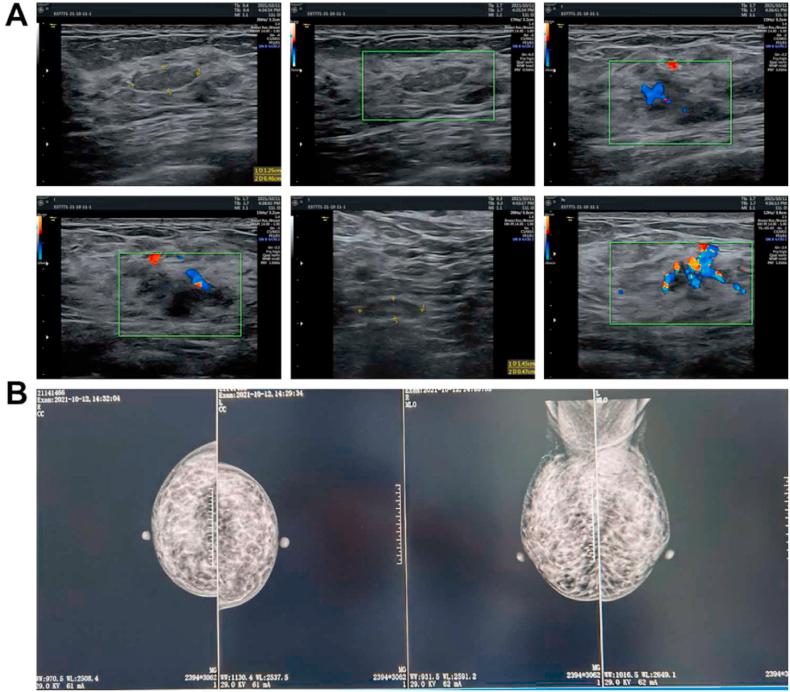

腺泡细胞癌(ACCA)是一种恶性上皮性肿瘤,多发生于腮腺,偶尔也见于乳腺。关于乳腺原发性ACCA的已发表文献较少,报告数量可能不足100例。目前,完整的临床细节尚未公布。作为一种极为罕见的疾病,ACCA不能仅依靠微观结构确诊,通常需要免疫组织化学的辅助。目前,尚无通用的治疗方法。在此,我们报告一名47岁患者,其左乳外上象限可触及肿块2年多,近半年明显增大。该患者被确诊为乳腺原发性ACCA。术前进行了新辅助化疗,术后基于原发肿瘤细胞进行了药敏试验,并成功为患者筛选出更有益的化疗方案。整个治疗过程遵循浸润性乳腺癌的治疗指南。患者术后14个月无症状。正在进行长期随访。总之,为进一步拓宽对乳腺原发性ACCA的认识,我们详细介绍了一名患者的诊断和治疗过程,并对相关文献进行了综述。